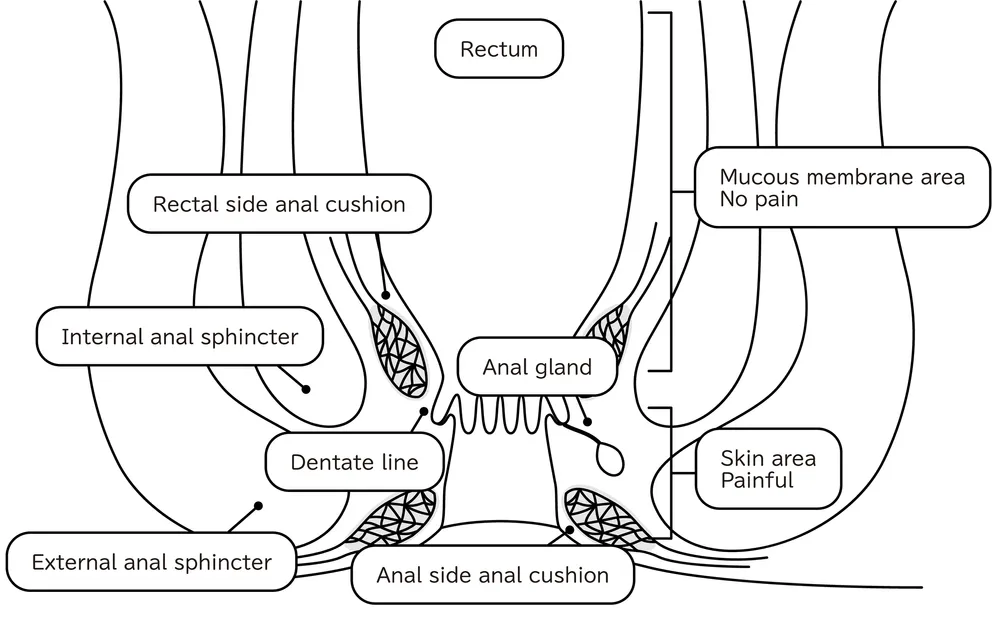

از نظر آناتومیکی، مقعد در امتداد کانال آنال (anal canal) قرار دارد و بافتهای متعددی آن را تشکیل دادهاند که هر یک وظیفهای مشخص و هماهنگ دارند. این بافتها را میتوان به دو دسته اصلی تقسیم کرد: بافتهای عضلانی و بافتهای پوششی.

در ناحیه مقعد دو دسته عضله عمده وجود دارد: عضله اسفنکتر داخلی و عضله اسفنکتر خارجی.

عضله اسفنکتر داخلی از نوع عضلات صاف است که کنترل آن غیرارادی بوده و بهصورت خودکار، در حالت استراحت، مسیر خروجی مقعد را بسته نگه میدارد.

عضله اسفنکتر خارجی از نوع عضلات مخطط است و تحت کنترل ارادی قرار دارد؛ این عضله در فرآیند دفع، مخصوصاً هنگام کنترل آگاهانه عمل دفع، نقش اساسی ایفا میکند.

سطح داخلی کانال مقعد با نوعی پوشش سلولی بهنام اپیتلیوم پوشیده شده است. قسمت ابتدایی کانال آنال دارای اپیتلیوم استوانهای ساده مشابه رکتوم است، اما در نزدیکی دهانه مقعد به اپیتلیوم سنگفرشی تغییر مییابد که با پوست ناحیه اطراف مقعد تداوم دارد. این تغییر تدریجی در نوع بافت پوششی باعث میشود که ناحیه مقعد به خوبی در برابر اصطکاک، آلودگی و تماس با مواد دفعی مقاومت داشته باشد.

۳. شبکههای عروقی و هموروئیدی:

در دیوارههای کانال مقعد، شبکههای متراکم و پیچیدهای از عروق خونی بهنام شبکههای هموروئیدی داخلی و خارجی وجود دارد. این عروق در تنظیم فشار داخل مقعد نقش دارند و در صورت آسیب یا التهاب میتوانند منجر به بروز بیماریهایی مانند بواسیر شوند.